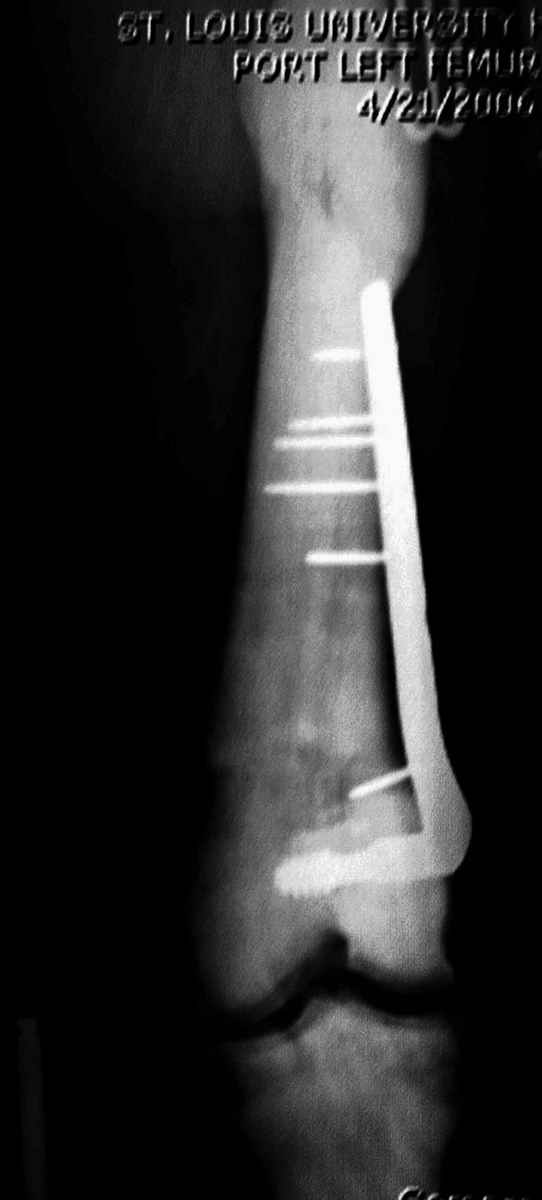

Любой стандартный штифт для проксимального отдела бедра пройдет. TGN действительно из всех самый короткий, и поэтому предпочтительнее.

Не вызывает ли подозрение, что отсутствует медуллярный канал, как просверлить канал?

1. Верхушку б\вертела всктыть спицей и рассверлить каннюлированным инструментом (14 мм).

2. Если в диафизарной части канал запаян, то, используя сам штифт, введенный в проксимальный отломок, как центратор, по нему завести спицу в центр дистального отломка и сформировать канал, сначала тонкий 4 мм.

3. Гибкими (неканнюлированными) развертками диаметром 6,7 и 8 мм последовательно расширить канал.

4. Рассверливать каннюлироваными развертками по направляющей спице до нужного диаметра.